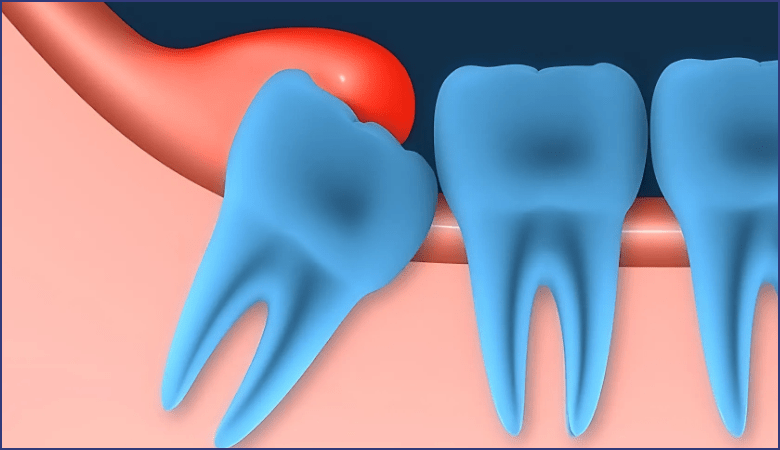

Răng khôn mọc lệch hoặc mọc ngầm

Quá trình mọc răng khôn thường khiến phần nướu phía sau hàm bị sưng đỏ, đau nhức do răng chen chúc hoặc đâm vào răng kế cận. Mảnh thức ăn dễ bị mắc kẹt ở khu vực này, hình thành ổ vi khuẩn gây viêm lợi trùm, dẫn đến sưng nướu, hôi miệng, thậm chí chảy mủ.

Quá trình mọc răng khôn cũng khiến phần nướu sau bị sưng đỏ (Nguồn: Internet)